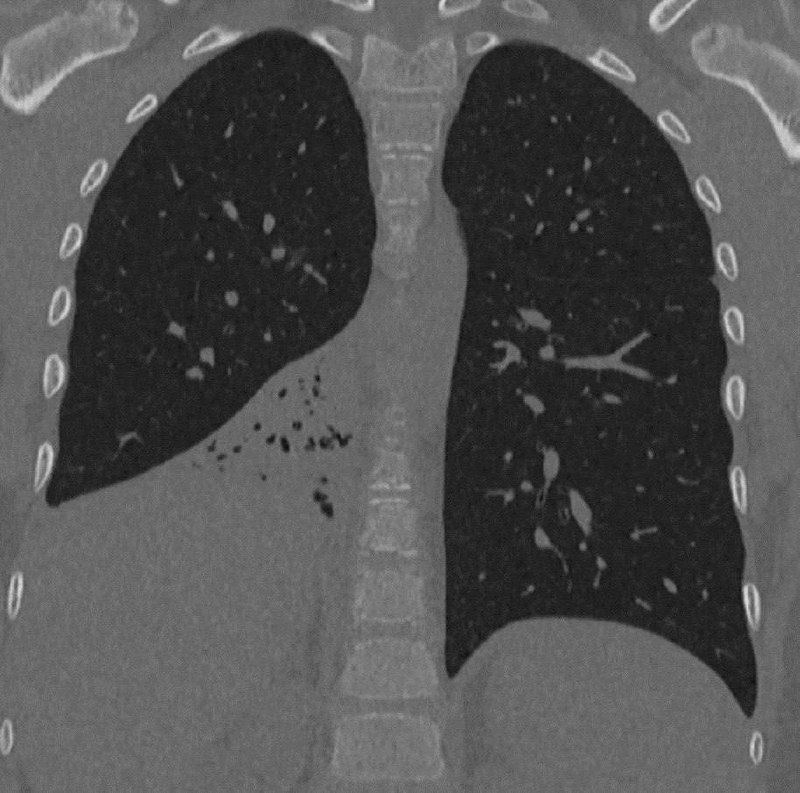

В Москве 8-летний мальчик полгода страдал от хронического кашля и подозрений на затяжную пневмонию.

И только спустя 6 месяцев врачи нашли настоящую причину — пластиковый колпачок от ручки, застрявший в бронхах. Ребёнок вдохнул его случайно и… молчал. Признался в этом уже после удаления.

📌 Инородное тело в дыхательных путях — редкая, но важная причина непроходящего кашля, хрипов и рецидивирующей пневмонии у детей.

📌 Оно может не вызывать острой реакции, но мешать вентиляции лёгких, способствуя воспалению и вторичной инфекции.

📌 Даже при «типичной» картине бронхита или пневмонии у ребёнка, который не реагирует на лечение, стоит подумать о рентгене или бронхоскопии — особенно если есть *односторонние изменения*.

🛑 Ребёнка спасла внимательность врачей и вовремя проведённая бронхоскопия. Операция длилась всего 30 минут. Сейчас он в порядке.